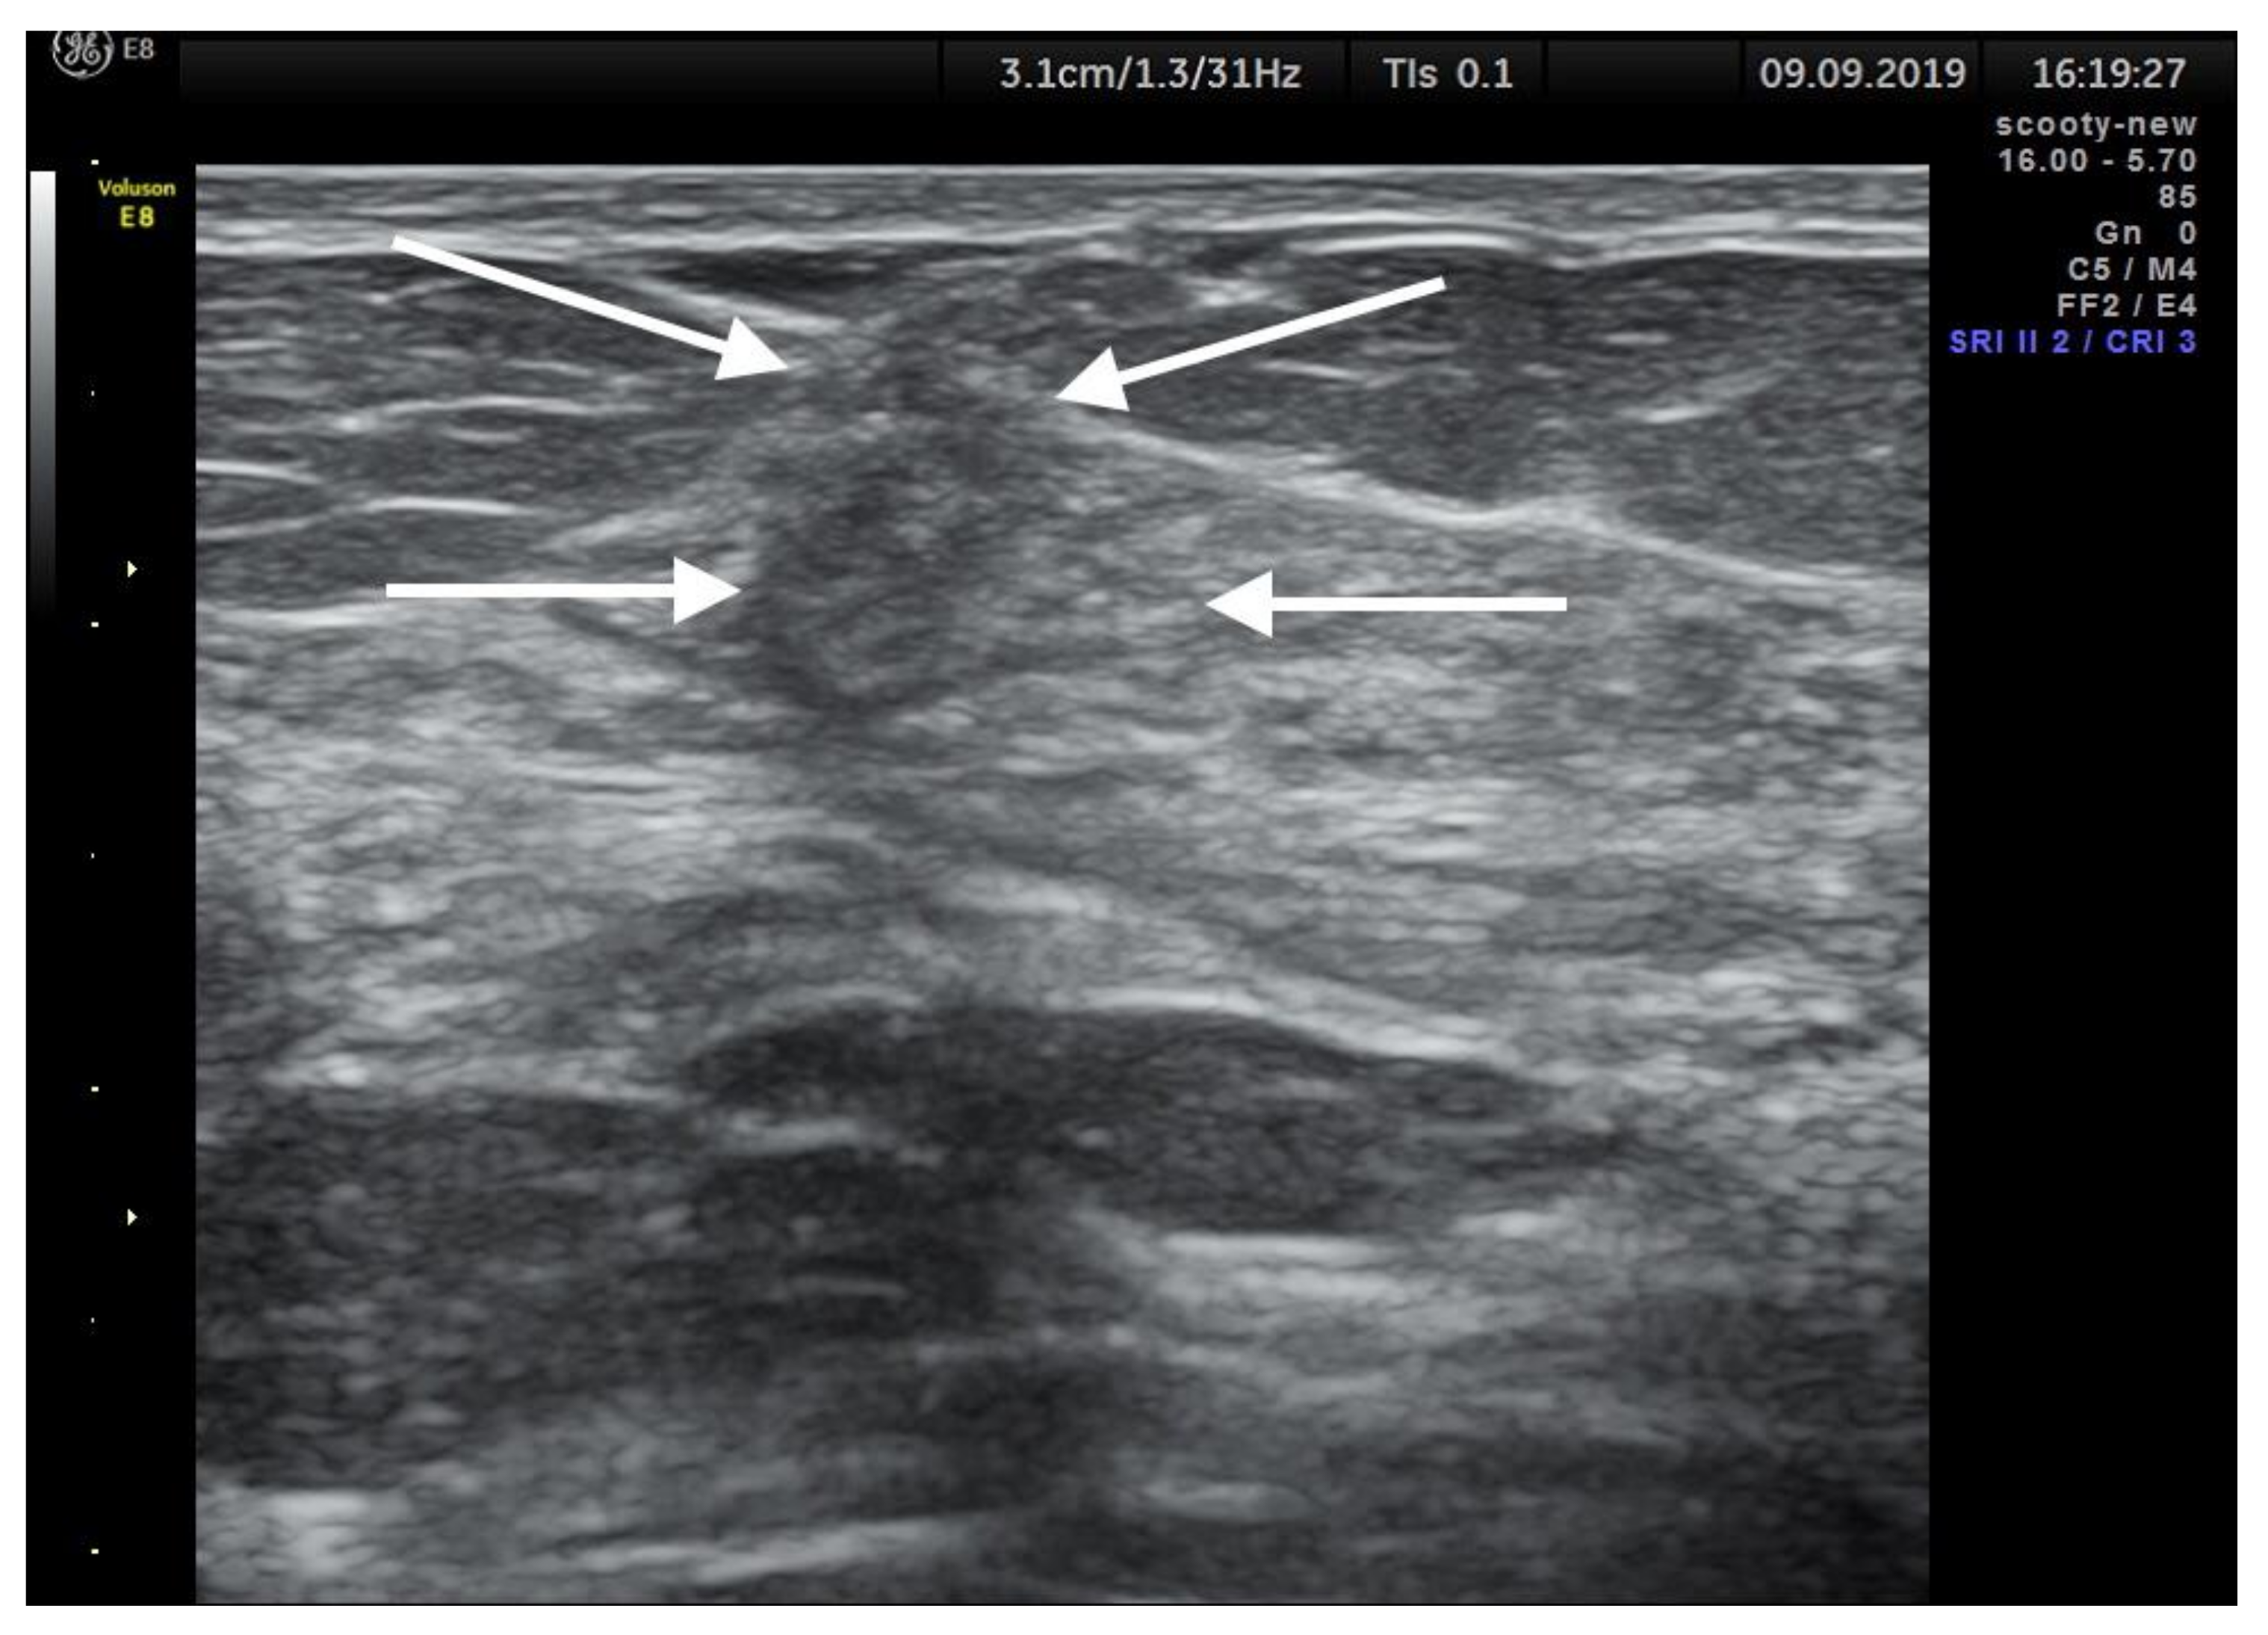

6. Imaging Findings